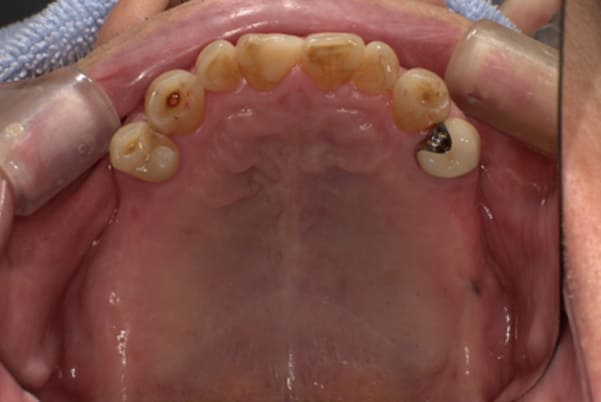

上顎治療前

-

上顎治療後

根のみの7本は虫歯にもなっており歯肉は腫れあがっています。

残りの歯もレントゲンで重度の歯周炎によりぐらぐらな状態でした。